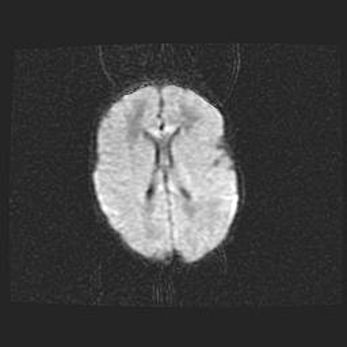

Сообщающаяся гидроцефалия. Кистозная энцефаломаляция головного мозга.

Возраст: 3 месяца 4 дня

Вес: 3100 г

Пол: женский

Окружность головы: 34 см

Срок гестации: 31 неделя

Кистозная энцефаломаляция головного мозга - одна из форм поражения головного мозга в детском возрасте. Характеризуется возникновением множественных и распространённых кист в коре, белом веществе и подкорковых образованиях головного мозга у плодов, новорождённых и детей раннего возраста. Развитие кистозной энцефаломаляции связано с внутриутробной асфиксией и гипотонией, родовой травмой, тромбозом синусов, пороками развития сосудов, инфекциями, сепсисом и другими причинами. Наиболее значимые инфекционные агенты: вирусы простого герпеса, цитомегалии, краснухи, токсоплазмы, энтеробактерии, золотистый стафилококк и другие.